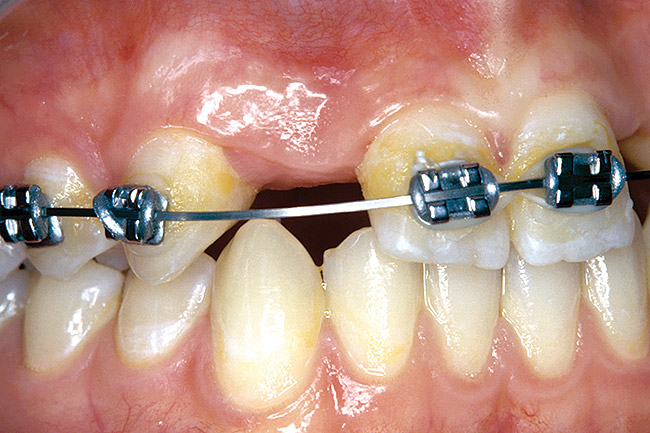

Periapical radiographs were taken to help determine the mesial-distal inclinations of the adjacent tooth roots (Figure 1). The radiographs revealed a serious issue, convergent roots for the right canine and right central, which eliminated that area as a potential implant-receptor site. The space between the left central and canine teeth was minimal, although the roots were relatively parallel. Clinical examination (manual palpation of the root eminences superiorly to the vestibule on the right side) confirmed the root convergence (Figure 2). The flat, wide zone of the keratinized tissue and lack of interdental papilla was evident for the missing right lateral incisor. There was a marked difference in clinical appearance for the left lateral, which could impact the eventual plan of treatment (Figure 3). Other significant clinical findings included bilateral facial bone concavities, which existed as a result of the congenitally missing tooth roots. As a diagnostic cue to the underlying bone topography, it is important to follow the demarcation between attached and unattached gingival tissue, and note the crestal width of the available keratinized tissue (Figure 4).

Figure 2  DIAGNOSTIC INFORMATION Root convergence, buccal view.

Figure 2

Figure 3  DIAGNOSTIC INFORMATION A difference in clinical appearance of the left lateral, buccal view.

Figure 3

Figure 4  DIAGNOSTIC INFORMATION Significant crestal width of keratinized tissue, buccal view.

Figure 4